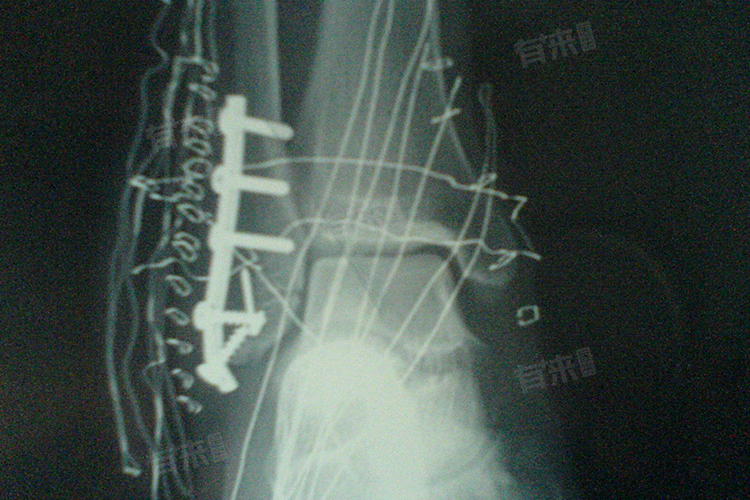

- 脚踝骨折取钢板是骨折治疗过程中的重要阶段,标志骨折部位已经愈合到了一定程度。尽管钢板已经取出,但骨折部位仍需进一步恢复和稳定。在取钢板后的初期,手术创口需要一定时间来愈合,同时骨折部位也需要适应没有钢板支撑的环境。患者不能立即下床走路,以免对伤口和骨折部位造成不必要的压力和损伤。

- 术后1周左右,伤口会逐渐消肿,疼痛也会有所减轻。但此时仍应避免下床走路,以免对伤口造成过大压力,影响愈合。随着时间推移,伤口和骨折部位的恢复情况会逐渐好转。大约在术后15天左右,如果伤口恢复良好,没有明显的红肿、渗出等情况,可以在医生的指导下尝试拄拐下地,进行部分负重行走。但此时仍需注意循序渐进,不可过度用力,以免对骨折部位造成不良影响。

- 到了术后1个月左右,大多数患者的骨折部位已经相对稳定,可以尝试脱拐行走。但此时仍需小心谨慎,避免剧烈运动和再次受伤。在康复期间,患者可以进行适当的康复训练,如踝关节的屈伸活动等,以促进关节功能的恢复。